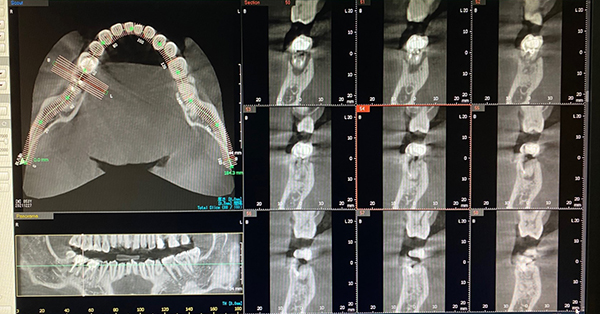

- CT撮影により

安全で正確な抜歯が可能

精密なCTデータで状態把握